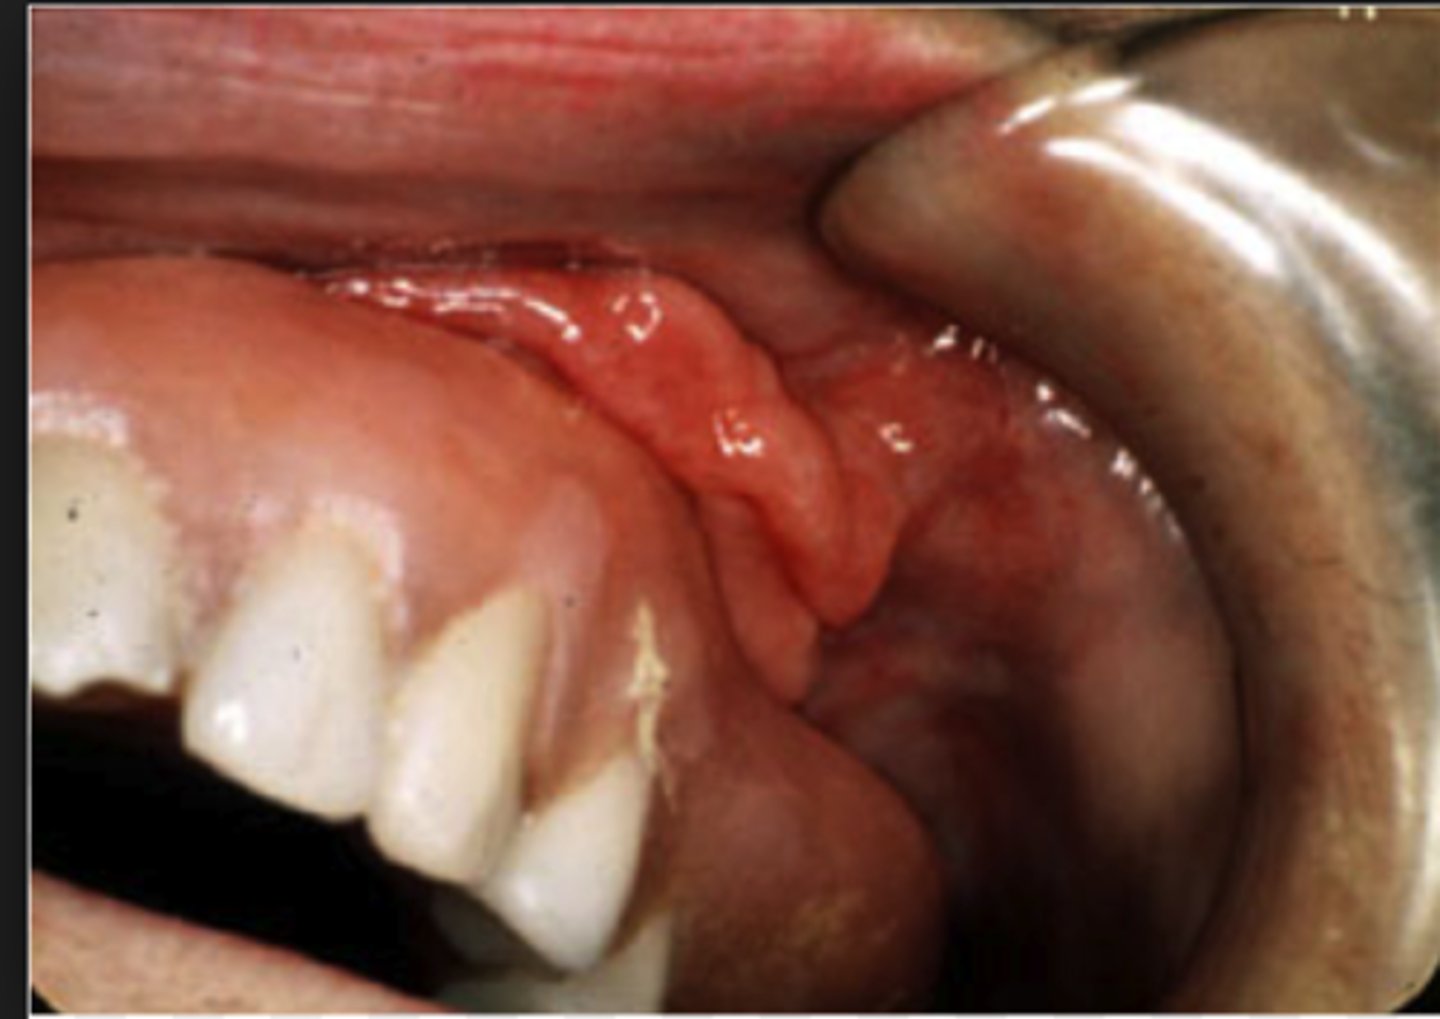

Picture of an epulis fissuratum. How do you treat this before making a new denture?

Excision.

[Other answer choices: Apply tissue conditioner, leave lesion alone, prescribe antibiotics] - Epulis fissuratum - benign hyperplasia of fibrous CT that develops as a reactive lesion to chronic mechanical irritation produced by flange of poorly fitting denture